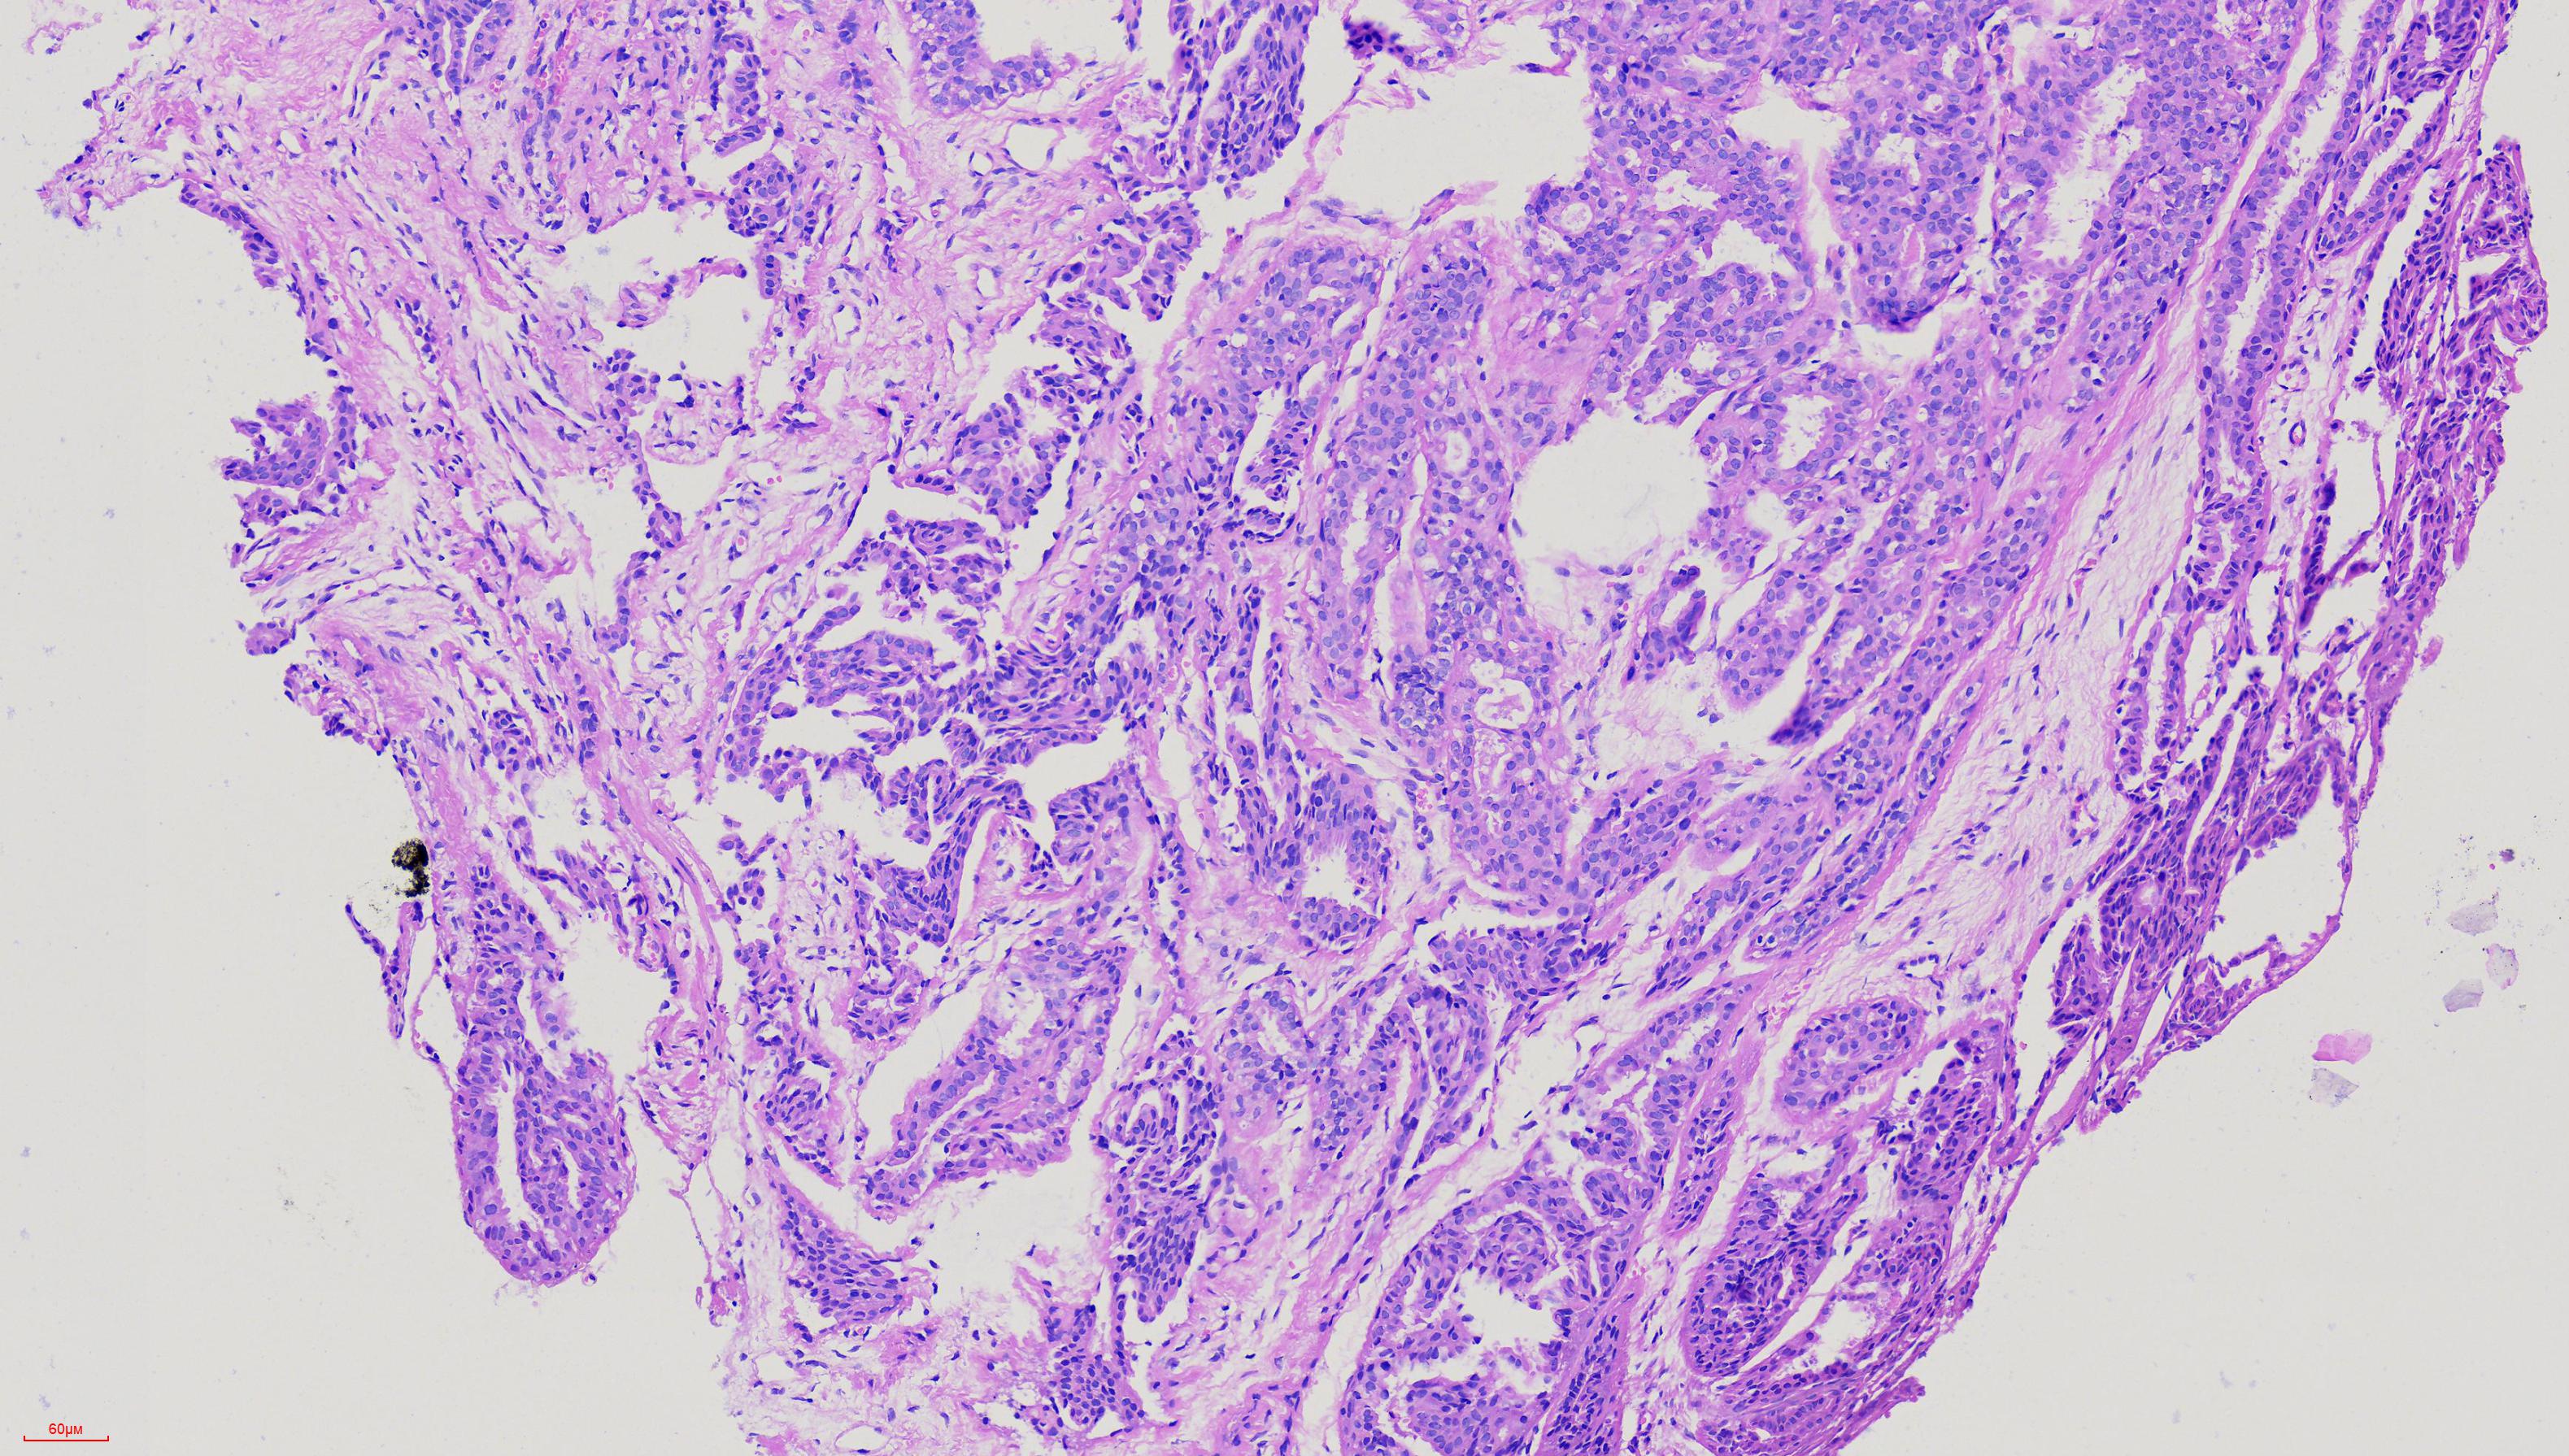

外阴肿物

性别

女

年龄

51岁

外阴肿物一年余

灰白色黄豆大组织

考虑为生乳头状汗腺瘤